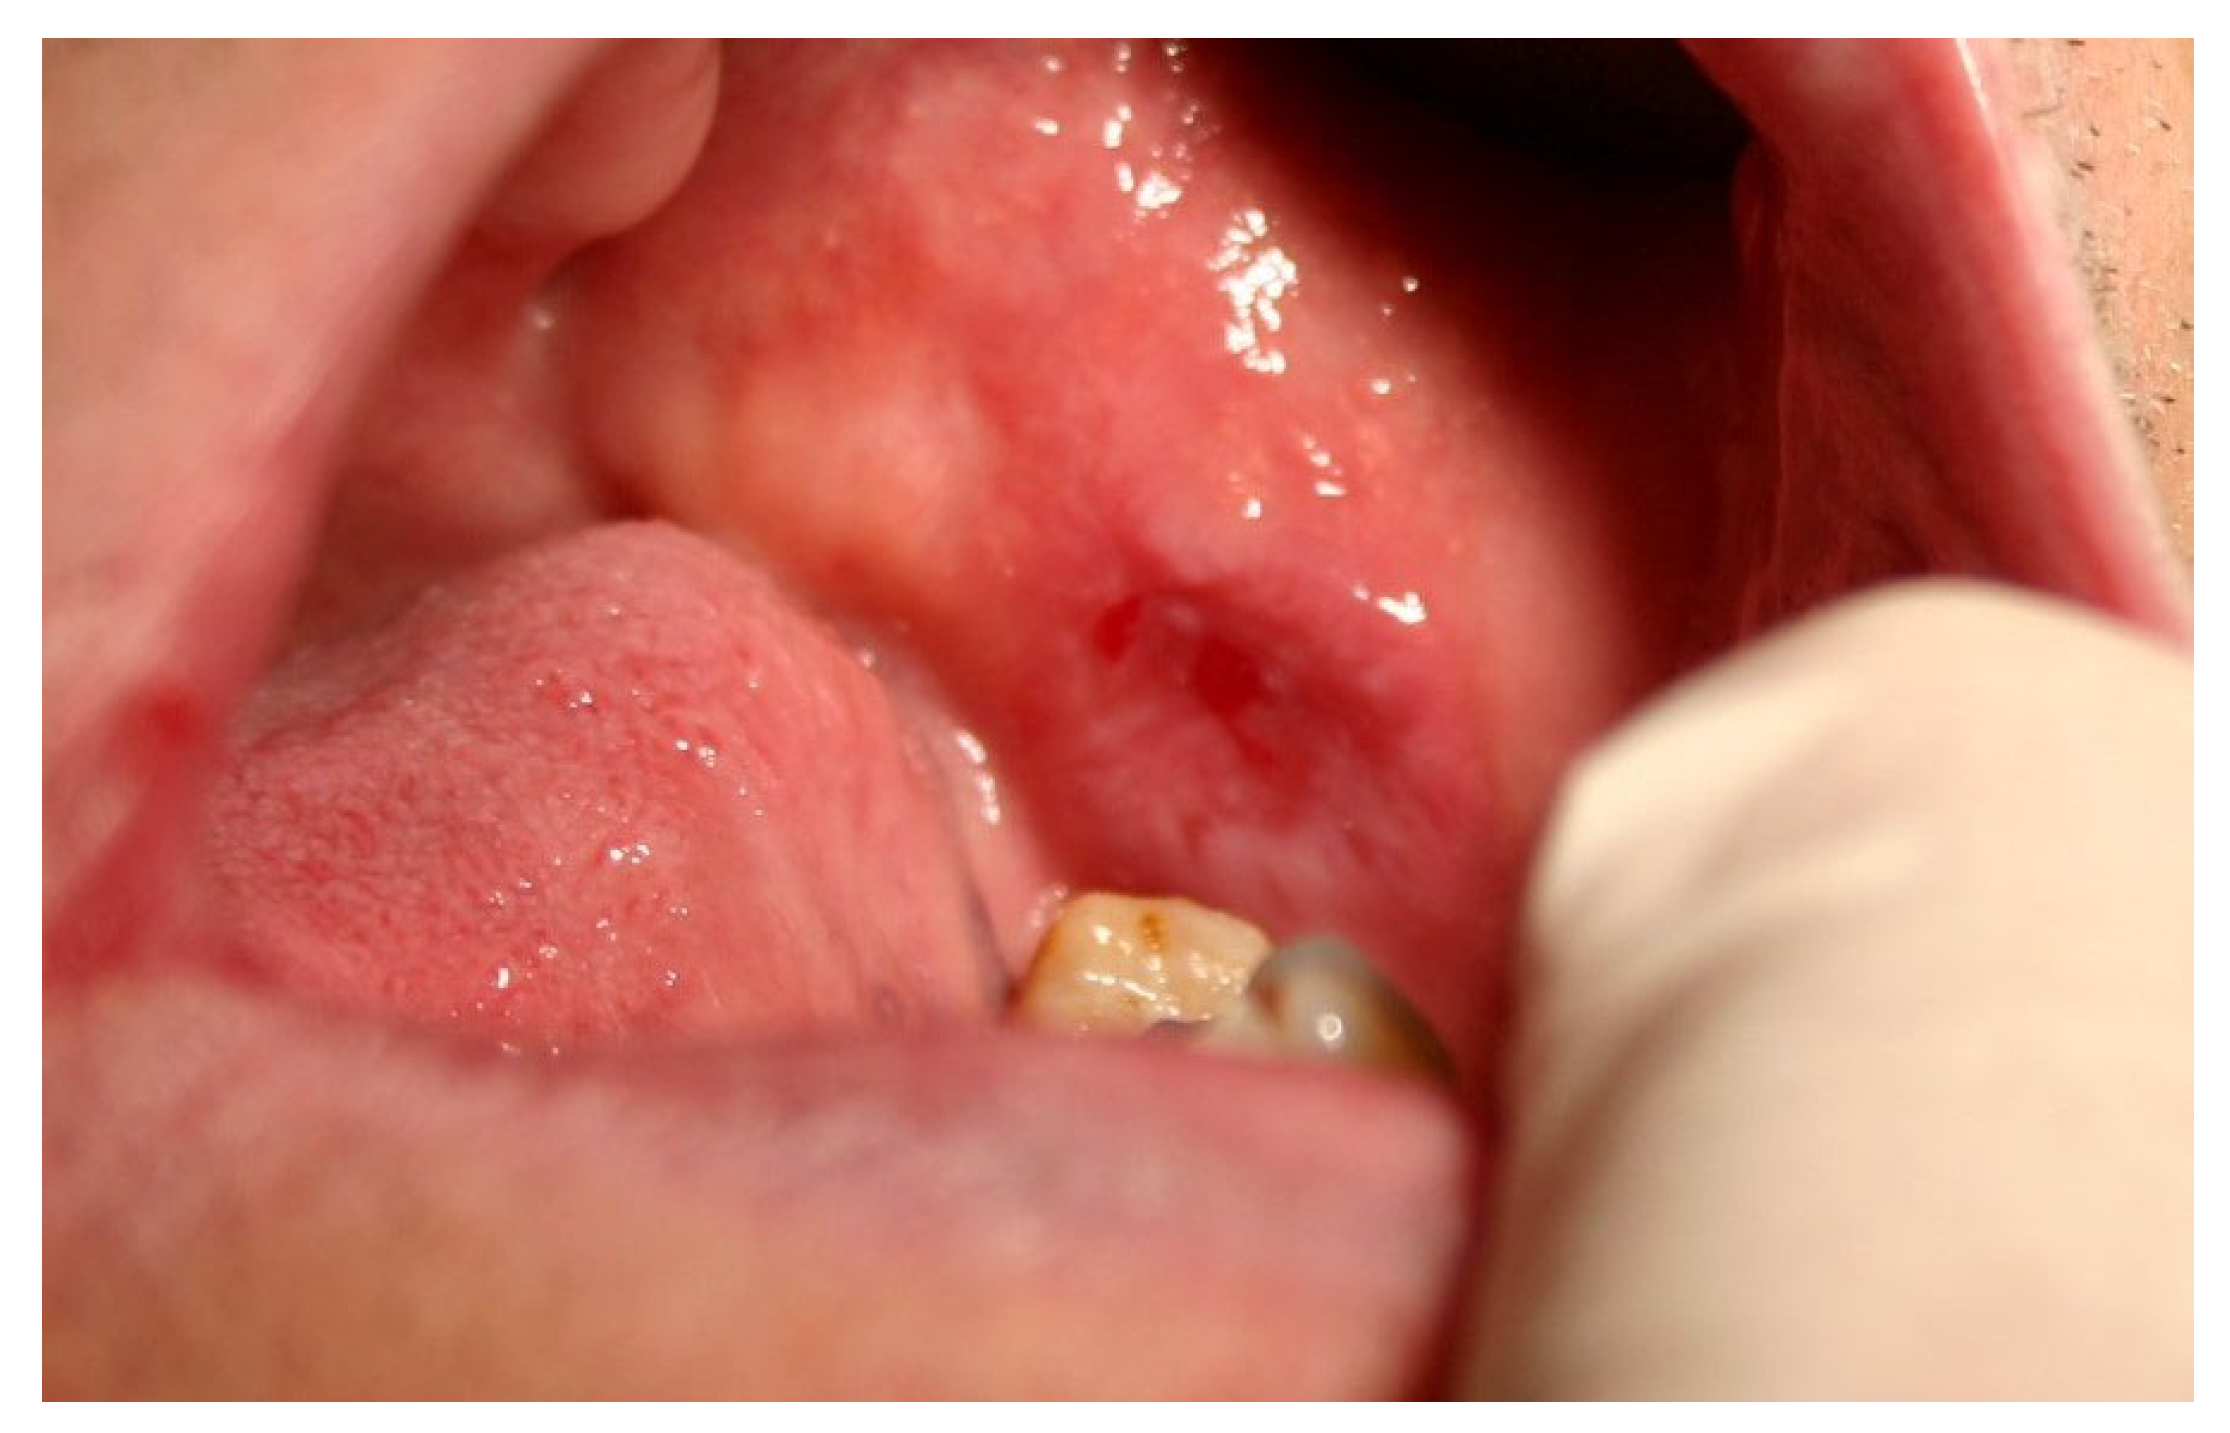

| Exfoliative (desquamative gingivitis) | 11 (5.8%) | 7 (5.4%) | 4 (7.1%) | 0.6520 | 2 (4.3%) | 9 (6.5%) | 0.5813 | 3 (10.0%) | 8 (6.2%) | 0 (0.0%) | 0.6224 |